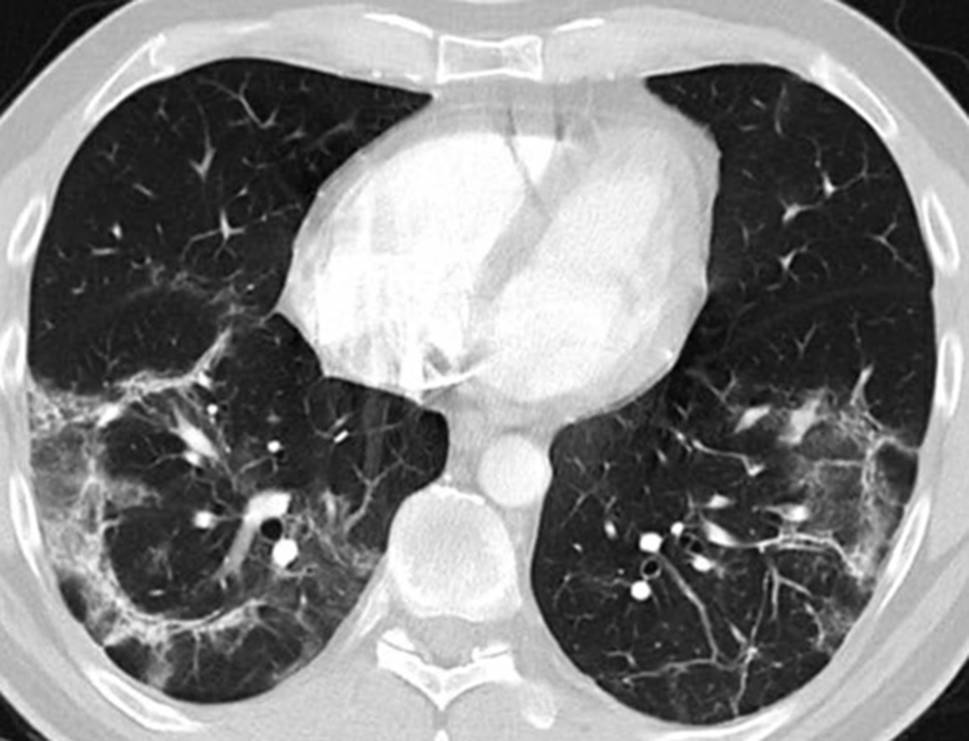

Fig. 4

Lung histology demonstrating micropolypoid buds of pale, myxoid granulation tissue in the alveoli. These granulation areas are known as Masson bodies, protruding into the alveoli and bronchioles (hematoxylin and eosin × 100)

On 27 April bronchoscopy was performed with the patient under general anesthesia. Endobronchial findings were normal. Bronchoalveolar lavage from the middle lobe showed 41% alveolar macrophages and 59% lymphocytes. T cells were minimally elevated and the CD4/CD8 ratio was normal. Activated T cells and natural-killer-like T cells were substantially elevated (19% and 25% of lymphocytes, respectively). Bacterial culture and SARS-CoV‑2 PCR from the lavage were negative. Cytology obtained by endobronchial ultrasound-guided biopsy of a mildly enlarged subcarinal lymph node showed normal lymphocytes. Lung histology obtained by fluoroscopy-guided transbronchial biopsy from the right lower lobe demonstrated granulation tissue in the alveoli and bronchioles, typical of organizing pneumonia (Fig. 4).